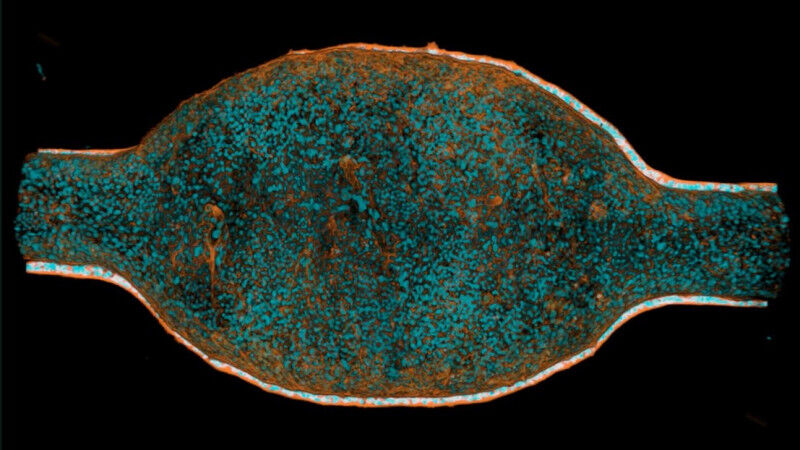

Wissenschaftler der EPFL, des Roche-Instituts für Humanbiologie in Basel und der Universität Heidelberg entwickelten eine menschliche Mini-Blase, indem sie die Organoid-Technologie und das Bioengineering kombinierten, um ein im Labor gezüchtetes Modell zu schaffen, das die komplexe Architektur des Organs nachbildet.Die Miniblase bildet die schichtweise Struktur der Innenwand der menschlichen Blase nach, setzt sie echtem oder synthetischem Urin aus und ahmt die Füllungs- und Entleerungszyklen nach. Auf diese Weise lässt sich beobachten, wie die Zusammensetzung des Urins die Gesundheit des Gewebes und das Überleben von Bakterien während einer Infektion beeinflusst.

Die Forscherinnen und Forscher kultivierten zunächst primäre menschliche Blasenzellen in einem kleinen Mikrofluidikgerät. Innerhalb weniger Wochen bildeten diese Zellen ein geschichtetes Urothel (die Innenwand der Harnwege) mit einer dichten Barriere, die der der menschlichen Blase ähnelte. Das Gewebe konnte sich dehnen und entspannen und so die Füllung und Entleerung der Blase nachahmen.Das Team perfundierte die Miniblase dann mit Urin unterschiedlicher Zusammensetzung, der jedoch klar definiert war. Es verglich einen Urin mit einer geringen Konzentration an gelösten Stoffen mit einem Urin mit einer hohen Konzentration an gelösten Stoffen. Die Wissenschaftler infizierten die Miniblase auch mit UPEC-Bakterien und verfolgten deren Auswirkungen in wiederholten Waschzyklen, die das Wasserlassen simulierten. Die Tests wurden auch in Gegenwart gängiger Antibiotika, einschliesslich Ciprofloxacin und Fosfomycin, durchgeführt